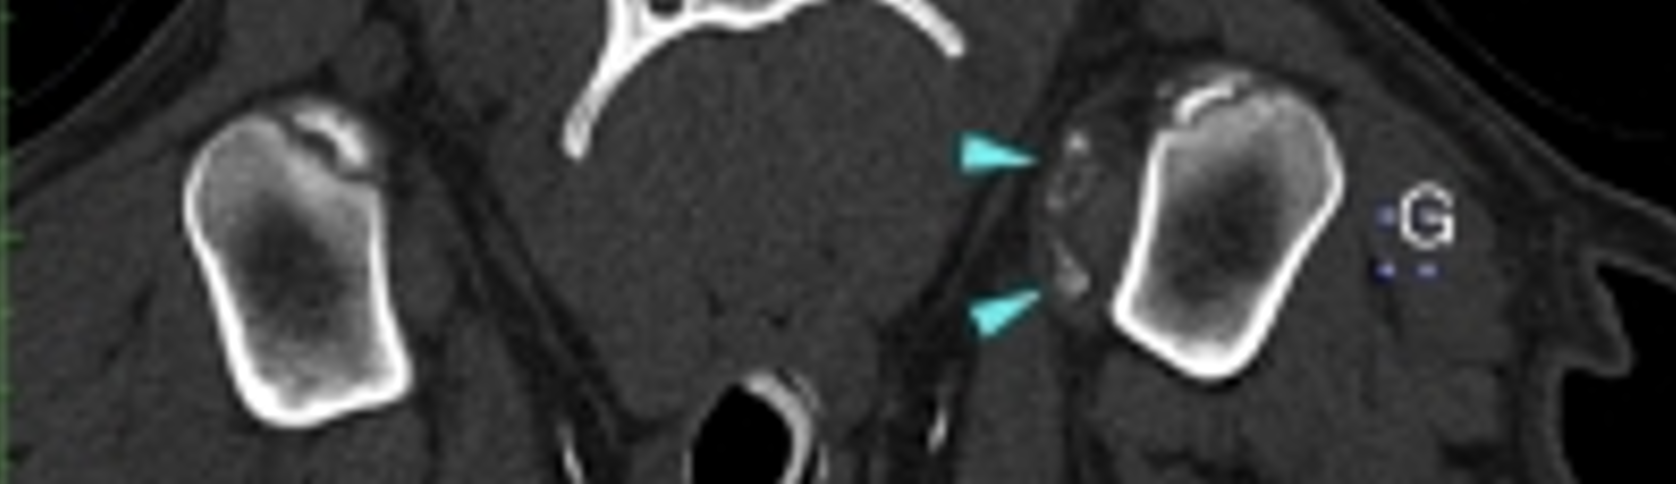

Un scanner des deux épaules et des coudes est réalisé. L’examen met en évidence des lésions d’ostéochondrite disséquante de la tête humérale gauche avec migration de deux volumineux fragments minéralisés (8x9x3 mm et 4x8x7 mm) dans la gaine du tendon du muscle biceps brachial (images 1, 2 et 3). L’épaule droite et les 2 coudes apparaissent peu remarquables.

Image 1 : fragments minéralisés dans la gaine bicipitale

Image 2 : deux fragments osseux médialement à la tête humérale